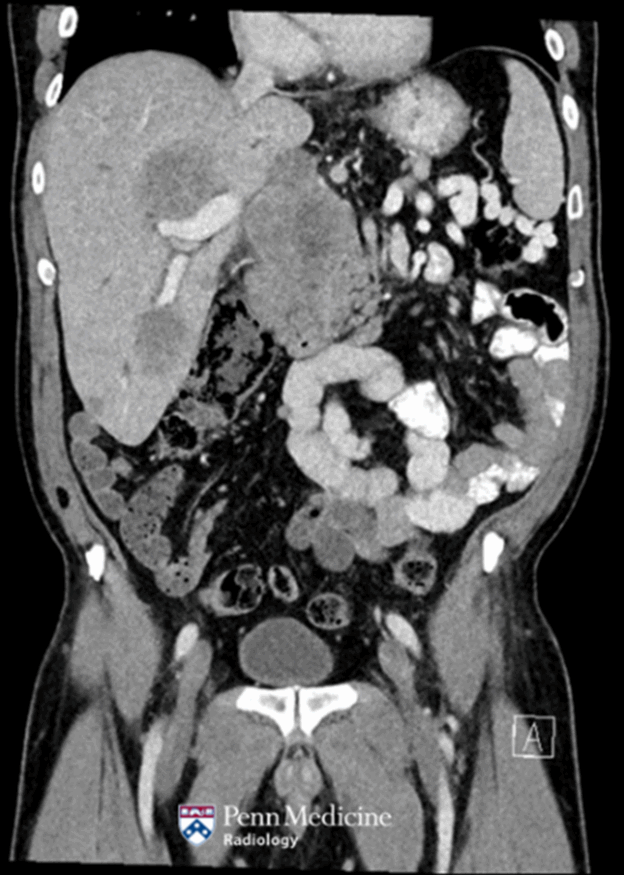

60-year-old man with weight loss, night sweats, melena

A 60-year-old man presented to the emergency department due to one month of loss of appetite, unintentional weight loss, night sweats, and melena.